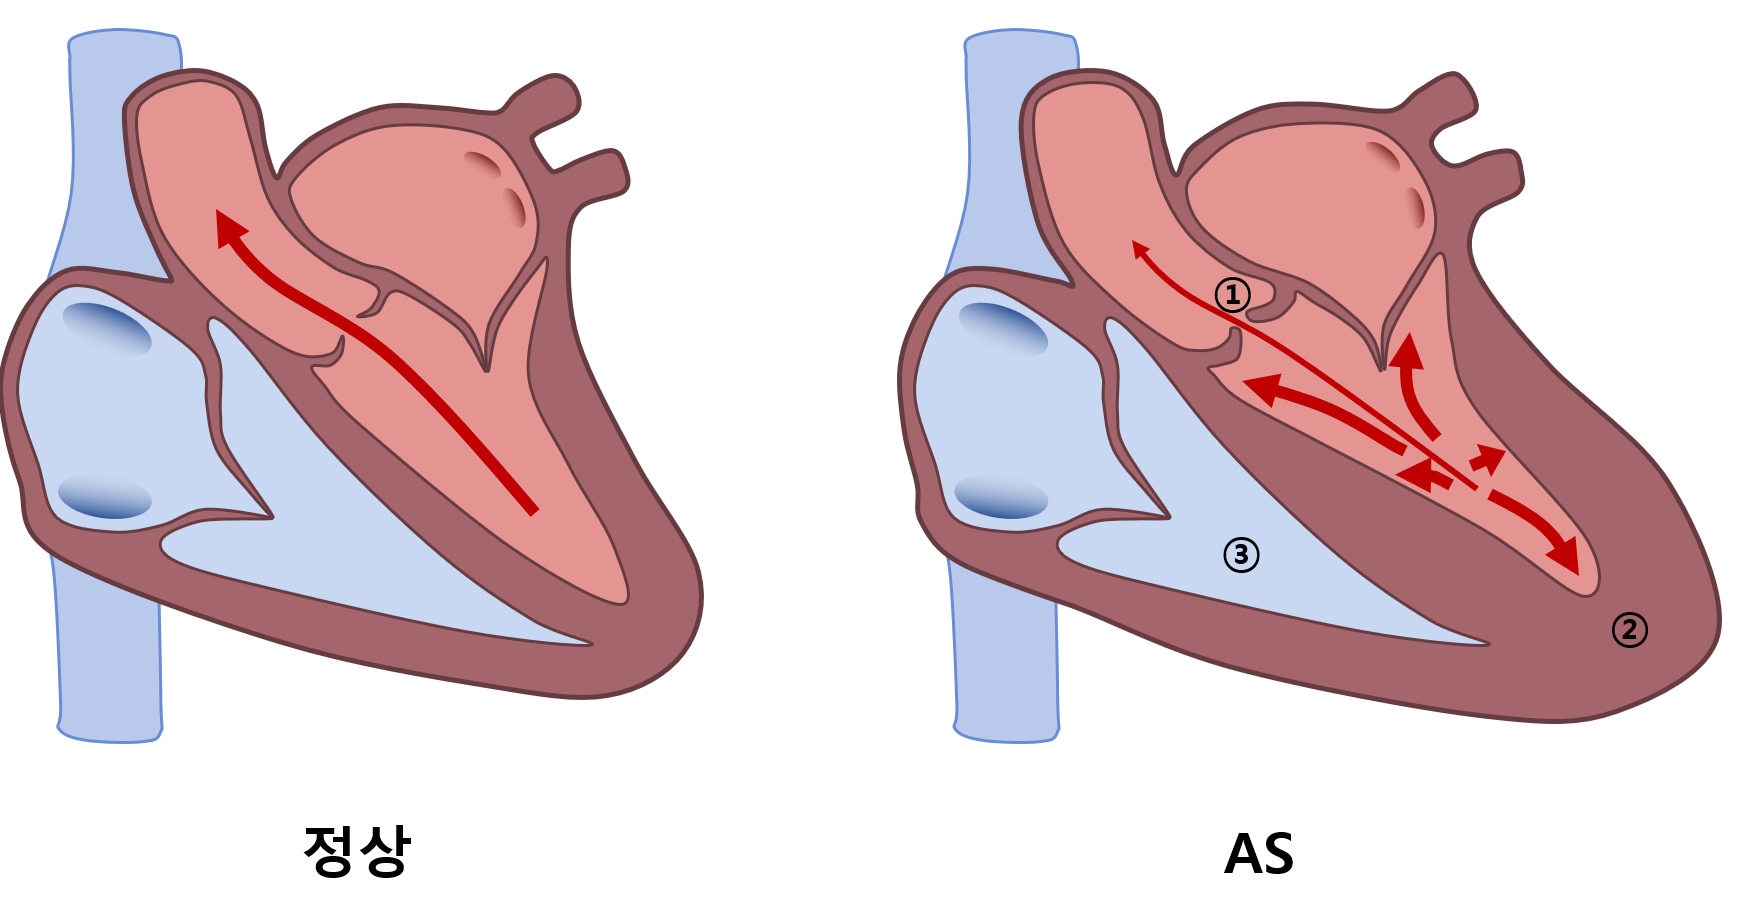

3) 병태생리

(1) 좁아진 aortic valve로 인해 afterload 증가 → LV pressure 증가

(2) 보상 기전으로 concentric hypertrophy → 지나친 심근비대, fibrosis 등에 의해 LV function 저하

(3) LV function 저하에 의한 LA, PA, RV 압력 증가 → RV function 저하도 동반 가능

(4) 심근비대에 의한 O2 demand 증가 + end-diastolic pressure 증가에 의한 coronary flow 감소 → ischemia